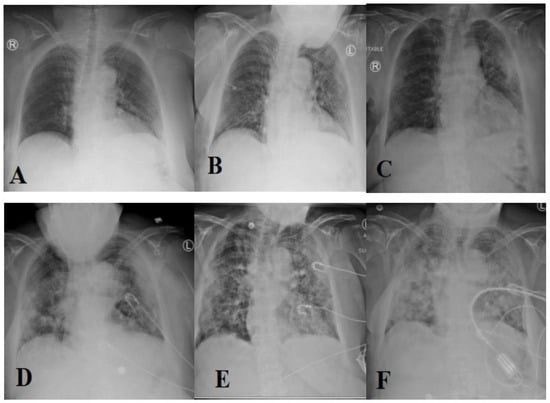

The most prevalent method of diagnosing individuals with respiratory disorders is chest radiography imaging [11,12,13]. At the beginning of COVID-19, a chest radiography image appeared normal, but it gradually altered in a fashion that may be associated with pneumonia or acute respiratory distress syndrome (ARDS) [11]. Figure 1 depicts the progression of chest X-ray images for a 45-year-old person infected with COVID-19. Roughly 15% of COVID-19 patients require hospitalization and oxygen therapy. Approximately 5% of people develop serious infections and require a ventilator.